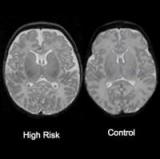

Известно, что шизофрению тяжело выявить до появления серьезных симптомов, связанных с маниями и галлюцинациями. Но к этому времени болезнь развивается до такой степени, что тяжело поддается лечению. Ученые из Университета Северной Каролины впервые выявили аномалии мозга, связанные с риском развития шизофрении у младенцев нескольких недель от роду. Таким образом, они смогут опознать детей, склонных к заболеванию, и принять соответствующие меры, считает Джон Х. Гилмор, профессор психиатрии. Они применяли ультразвук и МРТ, чтобы исследовать развитие мозга 26 младенцев, рожденных у матерей с шизофренией. Известно, что в таком случае риск болезни возникает у каждого десятого. Оказалось, что у мальчиков был больше объем мозга за счет боковых желудочков, заполненных жидкостью. Однако мозг девочек развивался одинаково, ведь известно, что шизофрения чаще появляется у мужчин. Результаты исследования не означают, что большой объем мозга обязательно указывает на шизофрению. Иногда врачи не обнаруживают у пациентов с этим диагнозом никаких изменений. Ученые собираются продолжить исследования, наблюдая за детьми в процессе развития моторных навыков и памяти. Источник: ScienceDaily